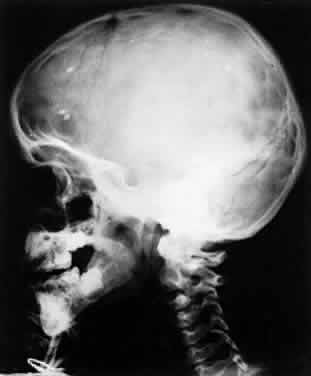

Clinical manifestations of congenital toxoplasmosis consist of retinochoroiditis, fever, hepatosplenomegaly, lymphadenopathy, jaundice, skin rash, petechiae, myocarditis, encephalitis, and retinochoroiditis. Patients may later develop hydrocephaly or microcephaly, cerebral calcifications, convulsions, and psychomotor retardation. The most common clinical manifestation of congenital toxoplasmosis is retinochoroiditis. The microcephaly, which is a severe form of disease, may occur after injury to the brain by the infectious process. The calcifications tend to be scattered throughout the brain substance in toxoplasmosis (Fig. 5), whereas in cytomegalic inclusion disease the calcifications tend to be paraventricular. This finding, however, varies and is not absolute.

Fig. 5. Cerebral calcification in congenital toxoplasmosis. (Christenson L, Beeman H, Allen A: Cytomegalic inclusion disease. Arch Ophthalmol 57:90, 1957)